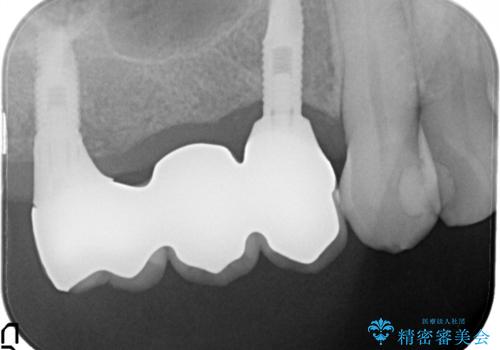

右の上下の歯を抜歯してインプラントを埋入して、かぶせ物を装着する計画としました。

右側のかみ合わせを回復するには、インプラントか入れ歯のどちらかの方法で治療する必要があました。

治療方法について十分な説明を行い、インプラント治療を選択されました。